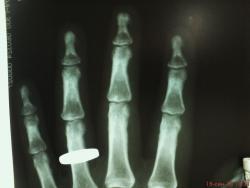

Сотрудница того же травм.пункта) лет 50. сразу извиняюсь за качество снимков. беспокоят боли в суставах кистей. меня заинтересовала структура кости в области ногтевых фаланг- уплотнение структуры, ногтевые фаланги смотрятся плотными. подобные изменения видел часто, но не в такой степени выраженности. может кто знает природу этого уплотнения и когда это встречается. и вообще - норма или нет. заранее благодарен.

это возрастные изменения в Рейнберге подробное описание,- я по поводу склероза; ну и кистовидная перестройка её как признак доа